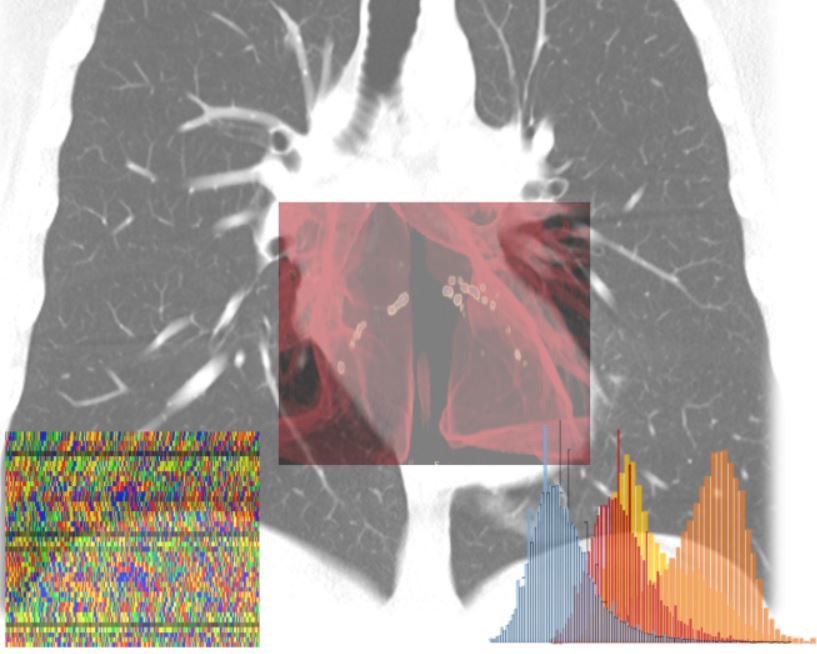

MILANO (ITALPRESS) – Una piattaforma di apprendimento autonomo in grado di calcolare per ogni individuo – sulla base di una serie di indicatori clinici e diagnostici – la probabilita’ di sviluppare le forme piu’ gravi di Covid-19, permettendo cosi’ interventi sanitari mirati e tempestivi e riducendo l’impatto sul sistema sanitario. E’ questo l’obiettivo del progetto AI-SCoRE (acronimo di Artificial Intelligence – Sars Covid Risk Evaluation) ideato dai professori Carlo Tacchetti e Antonio Esposito, entrambi docenti dell’Universita’ Vita-Salute San Raffaele, rispettivamente direttore e vice-direttore del Centro di Imaging Sperimentale dell’IRCCS Ospedale San Raffaele di Milano, e sviluppato in collaborazione con due colossi mondiali dell’information technology come Microsoft e NVIDIA, con il Centro di Omics Sciences dell’IRCCS Ospedale San Raffaele diretto dal dottor Giovanni Tonon, e con il supporto di due aziende: Orobix srl, societa’ attiva nell’ingegneria, produzione e governance di sistemi di AI con esperienza decennale e internazionale in ambito healthcare e Porini, centro di eccellenza e partner internazionale di Microsoft sulle piattaforme Cloud Azure e sulle soluzioni di Advanced Analytics.

La raccolta dei dati di oltre 2000 pazienti – reclutati fra Ospedale San Raffaele, Ospedale Bolognini di Seriate e Centro Cardiologico Monzino – e’ gia’ iniziata, cosi’ come la costruzione dell’infrastruttura software su cui poggera’ l’algoritmo.

“L’Intelligenza Artificiale (IA) sta aiutando a combattere la pandemia in molteplici casi d’uso. Le piattaforme IA di calcolo accelerato e il software di NVIDIA sono sfruttate in tutto il mondo per aiutare a sequenziare e analizzare i genomi virali e dei pazienti, monitorare la diffusione delle infezioni e l’andamento della mobilita’, accelerare lo sviluppo di nuovi farmaci e classificare e segmentare le immagini diagnostiche. Il progetto dell’ospedale San Raffaele stabilisce un nuovo punto di riferimento di qualita’ in termini di medicina personalizzata e NVIDIA e’ entusiasta di far parte di questa collaborazione”, afferma Francesco Torricelli, NVIDIA Country Director Italia & Iberia.